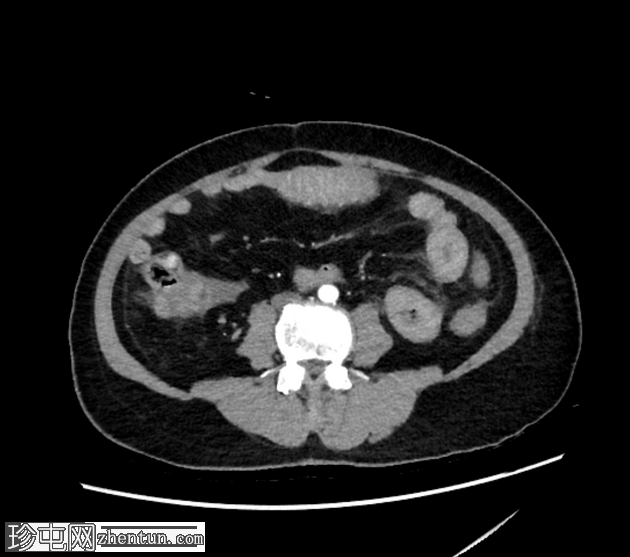

轴位增强扫描

动脉期

空肠(长段,60 cm)肠壁弥漫性节段性增厚。肠壁呈高密度影,平扫CT值约为56 HU,并可见强化。

可见肠系膜水肿和血管充血,以及少量腹水。

肠系膜上动脉和静脉通畅,未见血栓。

影像学表现最提示黏膜下出血。

鉴别诊断包括感染性肠炎。